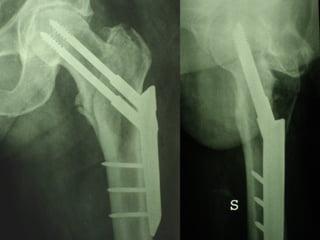

La placca a compressione percutanea (PC.C.P.) di Gotfried è un mezzo di sintesi studiato per assicurare un “impattamento controllato” delle fratture pertrocanteriche grazie alle due viti telescopiche prossimali che garantiscono una ottima stabilità rotazionale

Con la placca di Gotfried non si è mai riscontrato un danno iatrogeno del muro laterale e nessun collasso della frattura.Ciò è dovuto al fatto che i fori per l’applicazione delle due viti prossimali sono di piccolo diametro (9 mm) rispetto ai 16-32 mm necessari per introdurre la vite cefalica di un chiodo endomidollare o di una vite-placca a compressione.

La placca PC.C.P. viene inoltre applicata per via percutanea attraverso due piccole incisioni ottenendo in tal modo un minimo trauma chirurgico ed una  perdita di sangue estremamente ridotta in pazienti che per l’età  sono già in condizioni  critiche

Dal Gennaio 2005 ad Agosto 2006 110  placche di Gotfried Età media  : 78 anni (range 29-94) Tempo chirurgico: 30 minuti (range 12-45) IMMEDIATA CONCESSIONE DEL CARICO